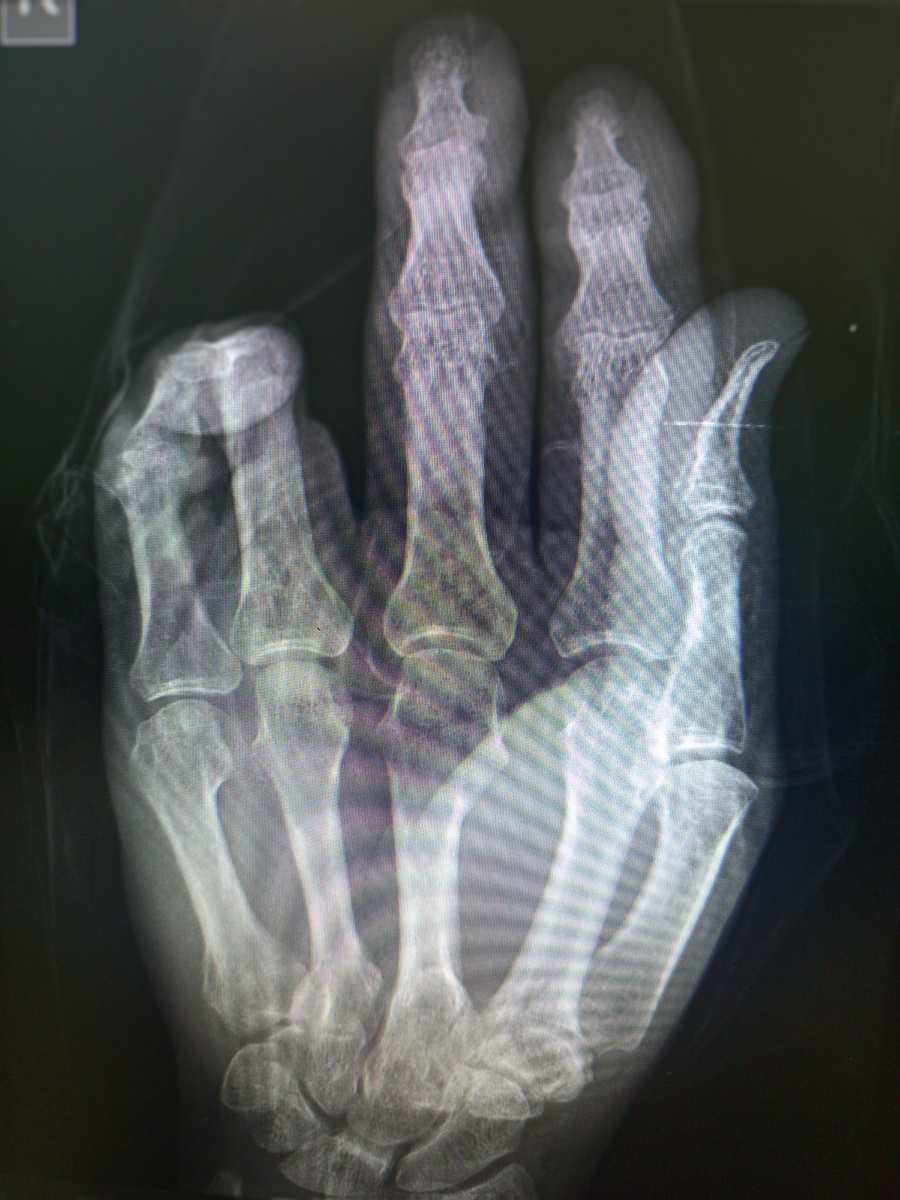

Мужчина 57 лет на снимок кисти пришел. Кисть замотана в платок.

Снимок неинформативен, но никто ему не будет убирать повязку в виде платка.

Сняла Борисовна , как есть.И через пять минут зазвонил телефон:

–Ага , угу, –говорит в трубку Борисовна. –Так а мы не обязаны раны разматывать, вы их сами размотайте, потом тогда на снимок присылайте! –положила она трубку.

–Кто там?

–Травматолог, не видно ему на снимке, что за травма.

Видимо , все сделали , потом на контроль прислали.